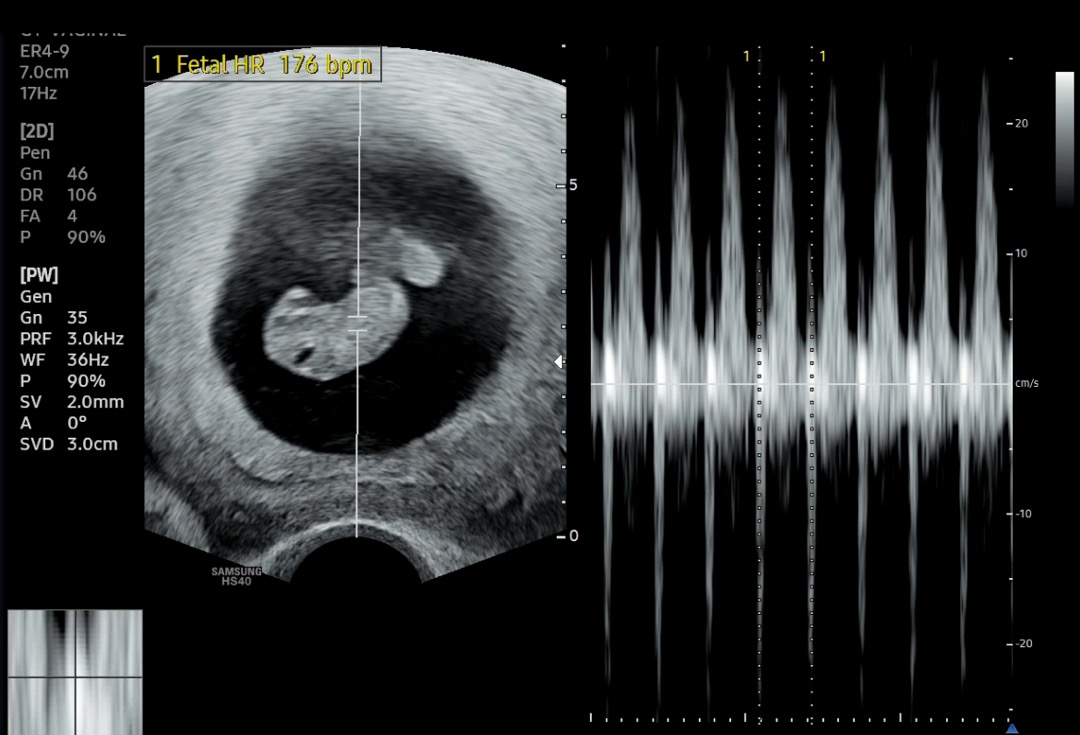

9주0일진료 봤는데 초음파상에는 8주6일이고 예정일도 하루 늦어졌는데요 크기 2.17cm 심장 176bpm나오고요 이때 쯤 젤리곰 보고 팔다리 본다하던데 아직 안보여서요 혹시 이런 경우 많은 가요?

저랑 같은 주수에 초음파 보셨네요~ 이게 초음파 각도에 따라서 젤리곰으로 보이기도하고 지금처럼 몸통만(?) 보이기도해요~ 제가 8주5일에 봤을때 젤리곰모양이었고 9주0일에 봤을땐 님하고 같은 모양이었어요!

저도 8주1일에 봤을땐 젤리곰 1.7cm , 2일 뒤에 다시 봤을땐 사진속 모양이였어요! 각도 같아요 ㅎㅎ